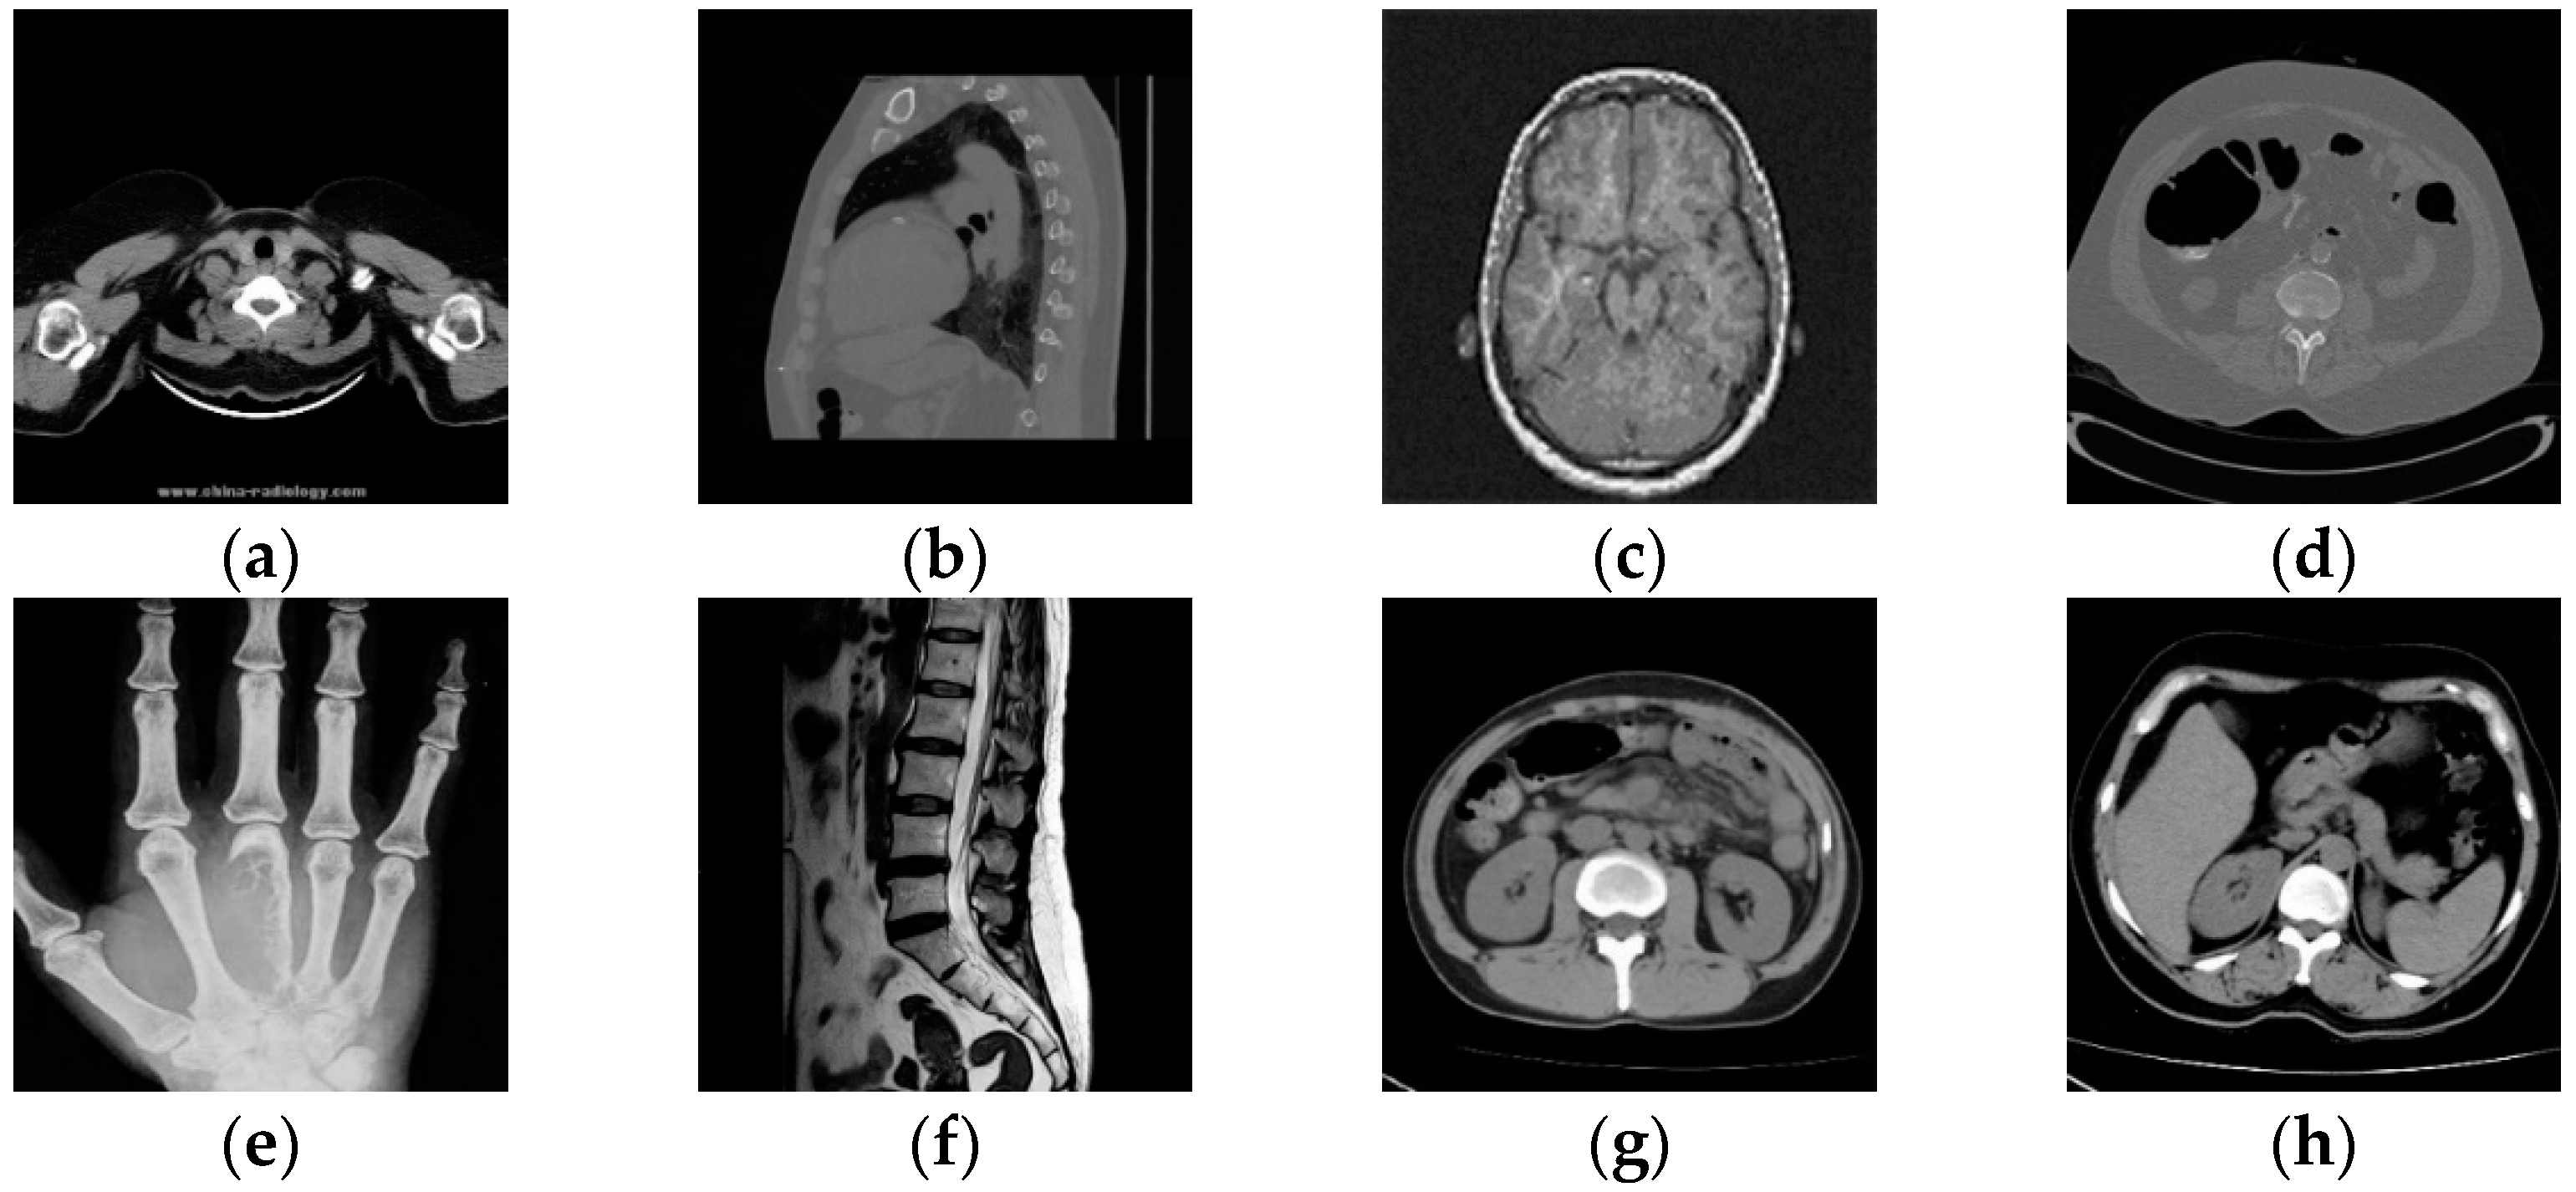

The medical image data selected for this paper comes from the Medical Imaging Park and American Research Institute, Inc., which contains tens of thousands of medical images. In this paper, we selected 125 medical images in each of the five major categories of brain, pelvis, bone and muscle, colon, and chest from the website as dataset 1, and encrypted these 125 medical images to obtain 125 encrypted medical images as dataset 2. Some of these 250 images are shown in Figure 5. Data sets 1 and 2 are completely disrupted, respectively, and then divided into three parts in the ratio of 3:1:1: the training set, validation set, and test set. In order to improve the robustness of the network in extracting features, in this paper, the training set and the validation set are enhanced with the data separately, as shown in Table 1. Thus, we obtained 12,850 images as the total dataset for this training. Because the input size of the DarkNet53 convolutional neural network is 2,562,563, all medical images are resized to 2,562,563 here. For the production of dataset labels, this paper first performs DCT on the images of the training and validation sets and then selects the 128-bit feature vectors of the low-frequency part as labels.

Figure 5.

Two original images and corresponding encrypted images for each type of image. Brain image (a); abdominal pelvis image (b); bone muscle image (c); colon image (d); and chest image (e).

In order to prove that the deep-learning algorithm proposed in this paper has certain reliability, eight medical images were randomly selected from the test set for testing, as shown in Figure 12. The NC is used to calculate the correlation between different images, and when the NC < 0.5, it indicates that the correlation between different image feature vectors is low, and the feature vectors extracted by this algorithm are representative. Table 2 shows the NC values between eight different cryptographic medical images. Since the absolute values of NC values of different images are less than 0.5 and the NC value of the same image is 1, the algorithm can distinguish different encrypted medical images and is reliable.

Figure 12.

Different medical images within the test (a–h), related encrypted images (i–p).